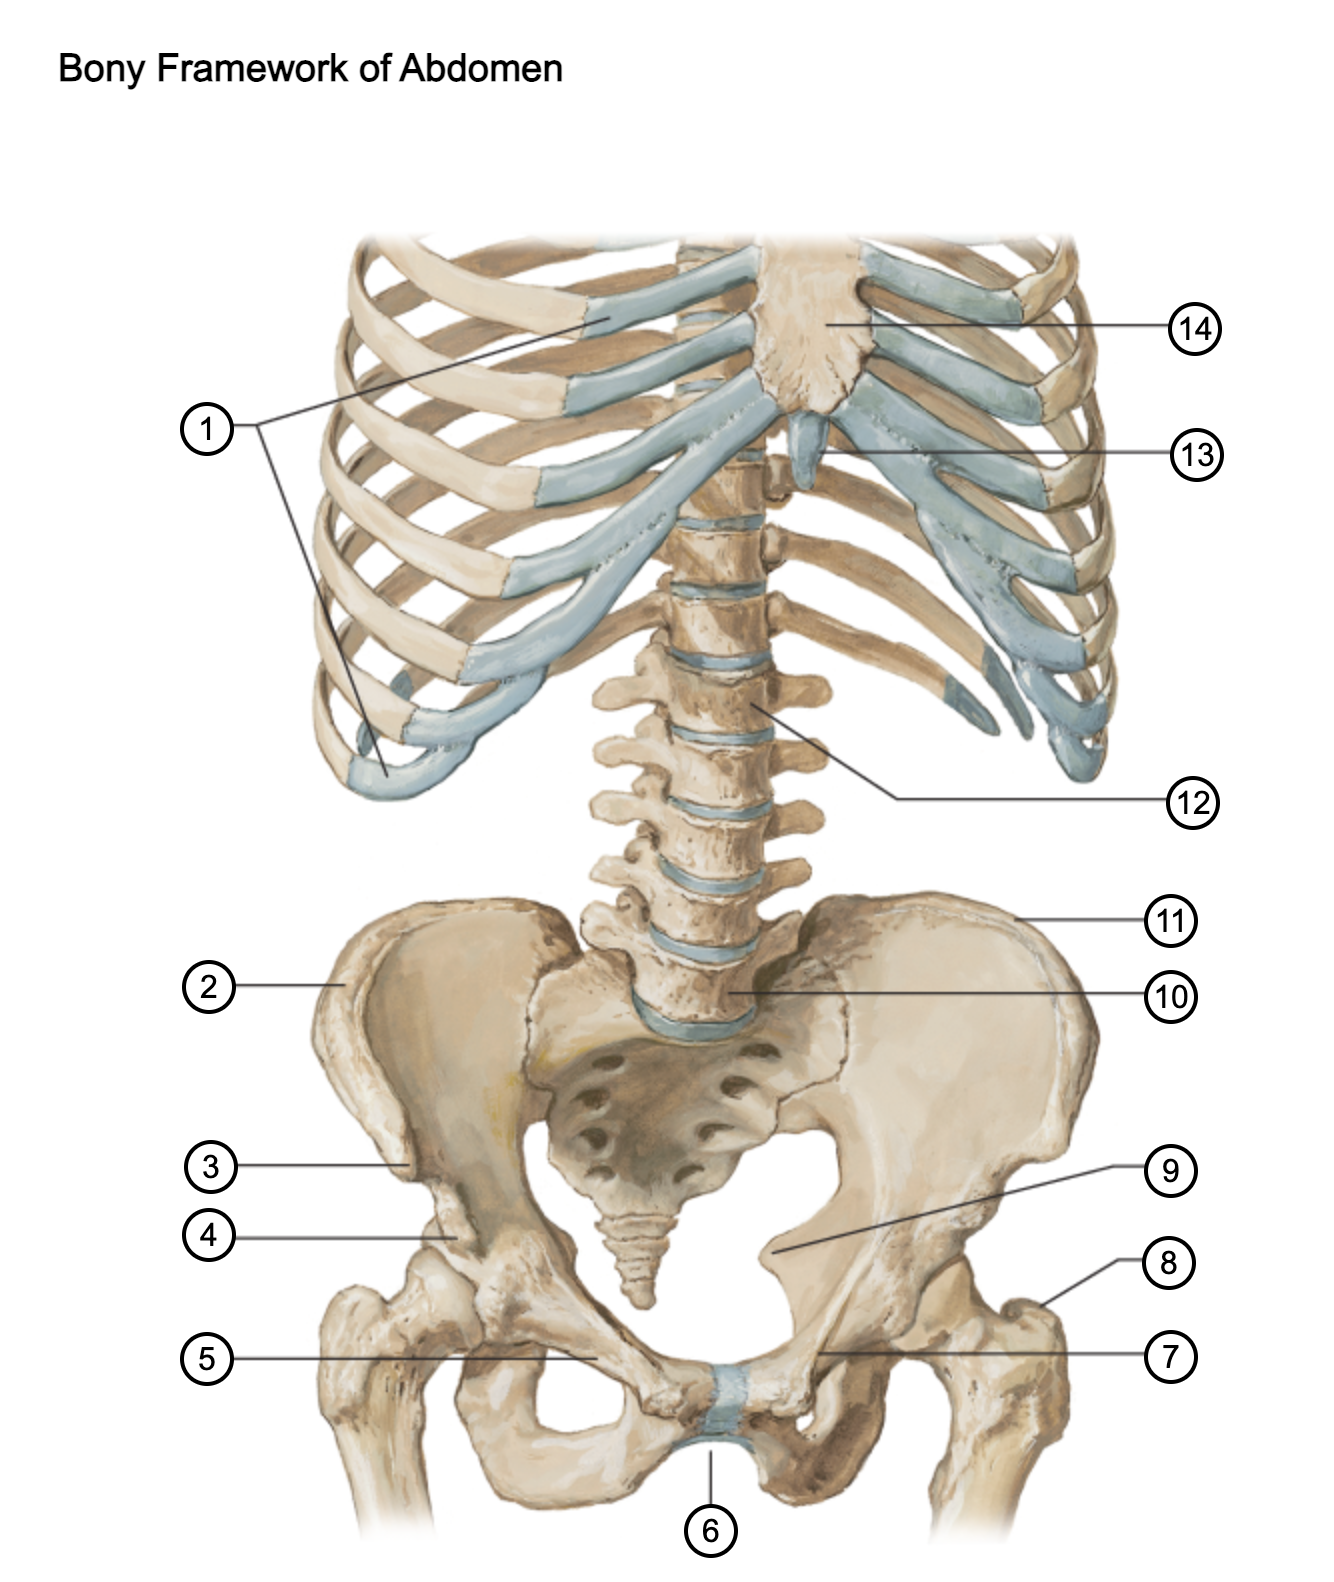

1

costal cartilages

2

iliac crest

3

anterior superior iliac spine

4

anterior inferior iliac spine

5

superior pubic ramus

6

pubic arch

7

pecten pubis

8

greater trochanter

9

ischial spine

10

L5 vertebra

11

iliac crest

12

L1 vertebra

13

xiphoid process

14

body of sternum